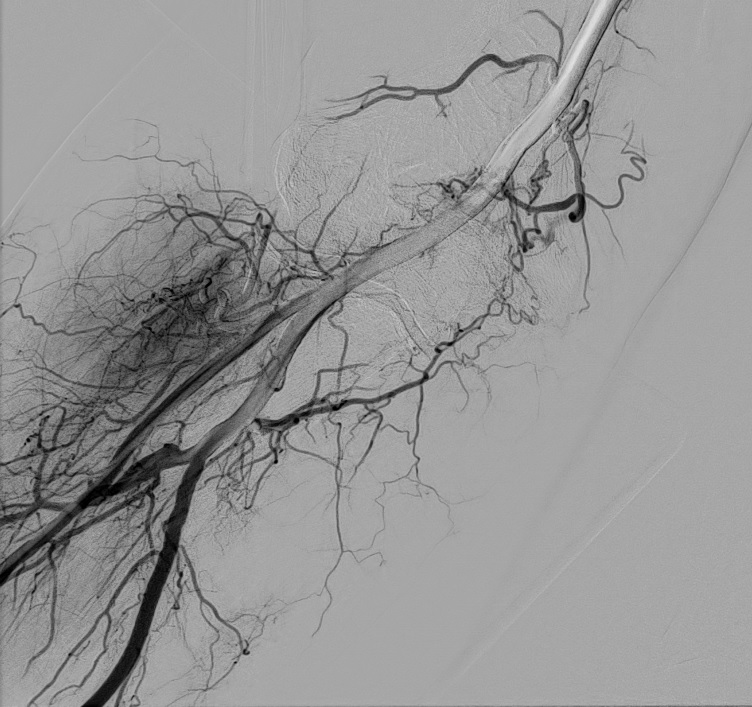

Une artériographie par injection de produit de contraste iodé est réalisée. Elle permet la cartographie des artères pour dépister les zones d'hypervascularisation, qui sont le témoin de l'inflammation locale. Ces zones sont le plus souvent concordantes avec les douleurs rapportées par le patient.

L'objectif de la procédure est de boucher (=emboliser) ces artères anormalement développées qui alimentent les zones inflammatoires du ligament, pour diminuer l'apport vasculaire et arrêter le cycle de l'inflammation.